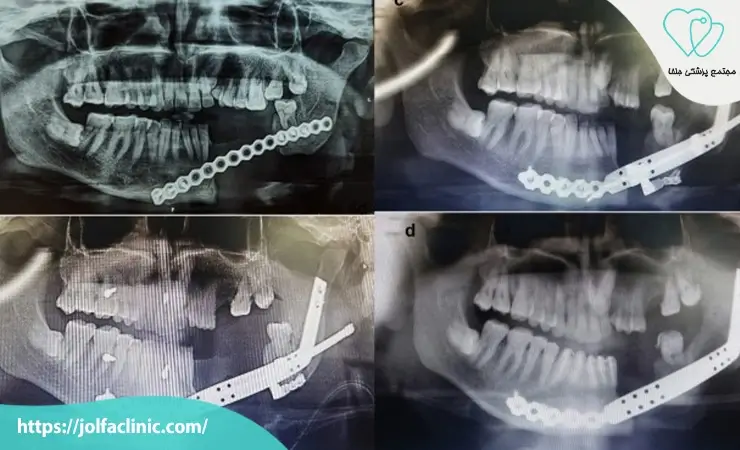

در شکستگی های گسترده، ممکن است چندین ناحیه از فک نیاز به تثبیت همزمان داشته باشد تا چهره به حالت طبیعی برگردد. استفاده از پلاک های تیتانیومی مانع حرکت استخوان در دوران ترمیم می شود. این جراحی ها در زمان مناسب می توانند از مشکلات طولانی مدت مانند بد بسته شدن فک جلوگیری کنند.

برای برنامه ریزی دقیق جراحی، از تصاویر سه بعدی CBCT یا عکس های پانورامیک استفاده می شود تا وضعیت استخوان، ریشه دندان ها و محل اعصاب مشخص گردد. این تصاویر به جراح کمک می کنند کمترین آسیب به بافت های حیاتی مثل عصب فک وارد شود. تصویر برداری مرحله ای حیاتی برای کاهش ریسک و افزایش دقت جراحی است.